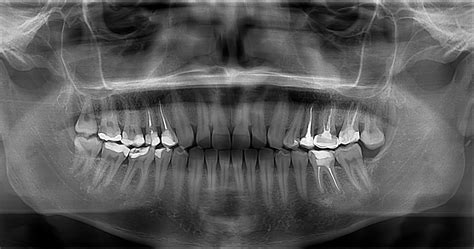

La radiografía panorámica utiliza un aparato especializado llamado ortopantomógrafo. Este dispositivo emite rayos X mientras gira alrededor de la cabeza del paciente, capturando múltiples imágenes que luego se combinan en una única representación bidimensional. Para realizar una ortopantomografía, el paciente debe colocar su cabeza dentro del ortopantomógrafo y morder un pequeño reborde de plástico mientras la máquina toma las imágenes.

El proceso para realizar una radiografía panorámica es sencillo y cómodo para el paciente. Tras retirar objetos metálicos como pendientes o collares que puedan interferir con la imagen, el paciente se coloca frente al aparato. La máquina rota alrededor de la cabeza en cuestión de segundos, emitiendo una dosis mínima de radiación ionizante.

Allí, el odontólogo accede a la radiografía panorámica para estudiarla y explicar al paciente todos los hallazgos que ha advertido. Una vez dicho todo lo anterior, es necesario resaltar que esta prueba no causa ningún tipo de dolor o molestia en el paciente. Además de que, como hemos mencionado ya, dura unos pocos segundos, el paciente no siente ni tiene que hacer nada mientras dura el proceso.

En cuanto a la seguridad, esta técnica utiliza una cantidad mínima de radiación ionizante, mucho menor que otras modalidades como la tomografía computarizada (TC). Esto reduce significativamente los riesgos asociados a la exposición a radiación, haciendo que sea apta para personas de todas las edades.

Hay determinadas personas que muestran preocupación ante el hecho de tener que someterse a una radiografía panorámica a debido a la radiación que provoca. Sin embargo, en Ferrus & Bratos contamos con un aparato de rayos X digital, el cual emite una radiación mínima, comparado con el convencional.